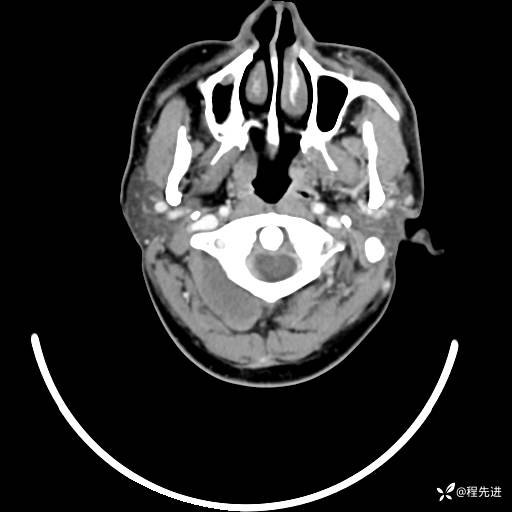

CT平扫+增强: